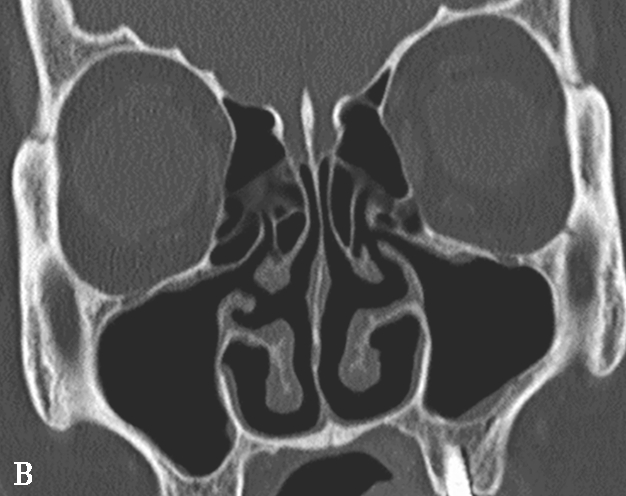

4.筛漏斗(ethmoidal infundibulum)

为筛骨钩突外侧与筛骨迷路间的漏斗形间隙,由前上向后下走行,前部较宽大,为额隐窝,当筛骨钩突前上部起自筛板外缘时,额隐窝为额窦的引流通道;外侧为上颌窦的自然开口;内侧为筛内钩突,后为上颌窦后囟(图1-3-5)。

图1-3-5 筛漏斗解剖

A、B.额隐窝(虚线),鼻丘气房(白箭),额气房(黑箭)